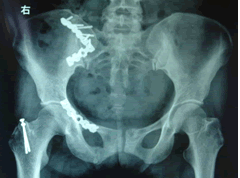

(1) 骨盆後前位X線片:X線平片檢查一般可明確骨折部位骨折類型及其移位情況,亦常能提示可能發生鵻的併發症。全骨盆後前位X線片可顯示骨盆全貌對疑有骨盆骨折者應常規拍攝全骨盆後前位X線片以防漏診對骨盆後前位X線片上顯示有骨盆環骨折者,為明確了解骨折移位情況還應再攝骨盆入口位和出口位片。

CT檢查對骨盆骨折雖不屬常規但它可在多個平面上清晰顯示骶髂關節及其周圍骨折或髖臼骨折的移位情況,因此凡涉及後環和髖臼的骨折應行CT檢查骨盆三維重建CT或螺鏇CT檢查更能從整體顯示骨盆損傷後的全貌,對指導骨折治療頗有助益但應銘記對血流動力學鵻不穩定和多發傷患者,後前位全骨盆X線片是最基本和最重要鵻的放射學檢查不要在拍攝特殊X線片上花費時間,更為重要的是儘快復甦。

對於大多數骨盆骨折來說,通過正位X線片就可以判斷骨折的損傷機制,決定最初的急救方案,其它的影像學檢查則有助於骨折分類及指導最終的治療方式。(一)、X線檢查

1、骨盆正位片。常規、必須的基本檢查,90%的骨盆骨折可經正位片檢查發現;

(二)、CT

CT是對於骨盆骨折最準確的檢查方法。一旦患者的病情平穩,應儘早行CT檢查。對於骨盆後方的損傷尤其是骶骨骨折及骶髂關節損傷,CT檢查更為準確,伴有髖臼骨折時也應行CT檢查,CT三維重建可以更真實的顯示骨盆的解剖結構及骨折之間的位置關係,形成清晰逼真的三維立體圖像,對於判斷骨盆骨折的類型和決定治療方案均有較高價值。CT還可以同時顯示腹膜後及腹腔內出血的情況。